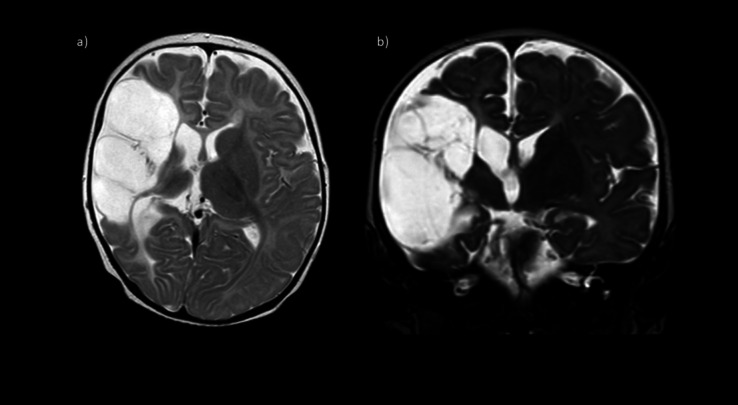

Infantile antiphospholipid syndrome (APS) is a rare condition arising from either transplacental transfer of antiphospholipid antibodies (aPL) from the mother or de novo antibody production in the newborn. We present a unique case of cerebral artery thrombosis with persistently elevated anti-cardiolipin and anti-β2-glycoprotein-I antibodies, despite the absence of maternal aPL, suggesting primary de novo aPL synthesis. While the prevailing "second-hit" hypothesis suggests that additional thrombotic risk factors are required to trigger APS in infants, our case exhibited no prenatal, maternal, or thrombophilic risk factors. A literature review of 20 reported cases further confirmed that ours was the only case without additional thrombotic triggers among the 18 cases with complete data, challenging the necessity of a "second hit" in neonatal APS. Notably, aPL levels normalized over time without recurrence, raising questions about the need for long-term anticoagulation in select cases, including ours. These findings suggest a potential transient form of infantile APS and highlight the importance of sequential aPL testing to guide treatment. Further research is required to elucidate the mechanisms underlying de novo aPL synthesis and its clinical implications.